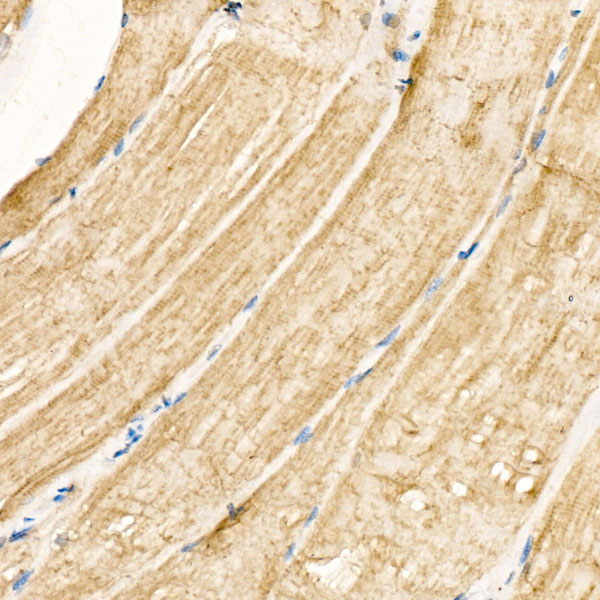

Immunofluorescence analysis of paraffinembedded Mouse heart using CHRNA1 Antibody at a dilution of 1:100 (40X lens);

Secondary antibody: Cy3 Goat Anti-Rabbit IgG (H+L) at 1:500 dilution;

Blue: DAPI for nuclear staining;

Perform high pressure antigen retrieval with 0.01 M citrate buffer (pH 6.0) prior to IF staining.